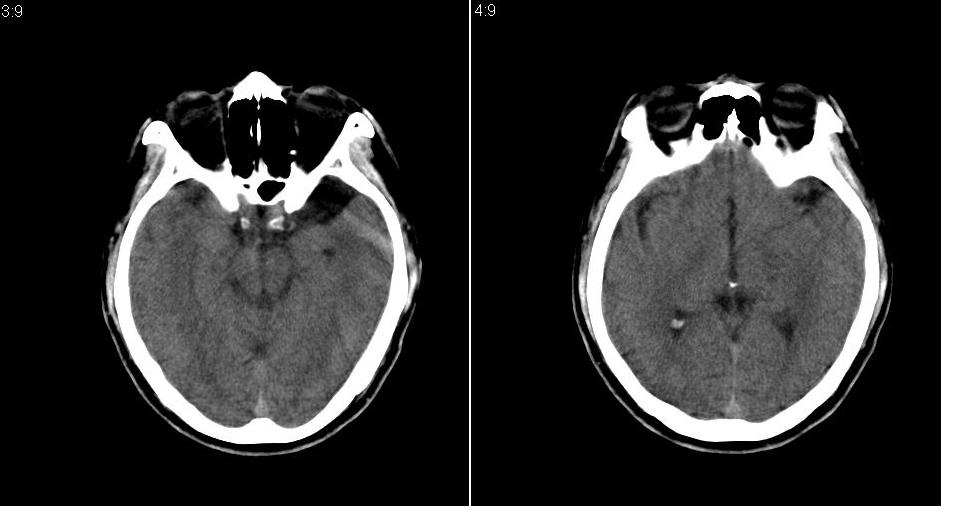

男 32岁,外伤。

大枕大池、左侧外侧裂池区蛛网膜囊肿

大枕大池、左侧外侧裂池区蛛网膜囊肿 。目前只能看到这些。

支持左侧中颅窝蛛网膜囊肿。

大枕大池、左侧颅中窝蛛网膜囊肿.